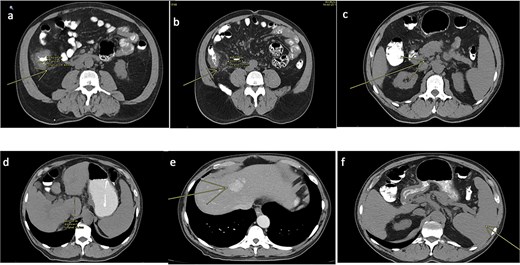

Given the appearance of the ascitic fluid (Fig. 3), a diagnostic paracentesis was performed. The fluid analysis showed leukocyte count of 12 362/μL (81.7% polymorphonuclear cells), and triglyceride level of 981 mg/dL, consistent with chylous ascites.

Image of chylous ascitic fluid collected through the abdominal drain, showing its characteristic milky appearance.

The drain output was monitored daily (Fig. 4). By hospital day 5, the output had decreased to 430 cc/day, and the fluid had become clear (Fig. 5). A soft diet was reintroduced. On day 6, repeat fluid analysis revealed a triglyceride level of 123 mg/dL, indicating resolution of the chylous leak. The patient was discharged on day 7 with outpatient follow-up.

Image of ascitic fluid on day 5 of hospitalization, showing clearer appearance indicating reduced chyle content.